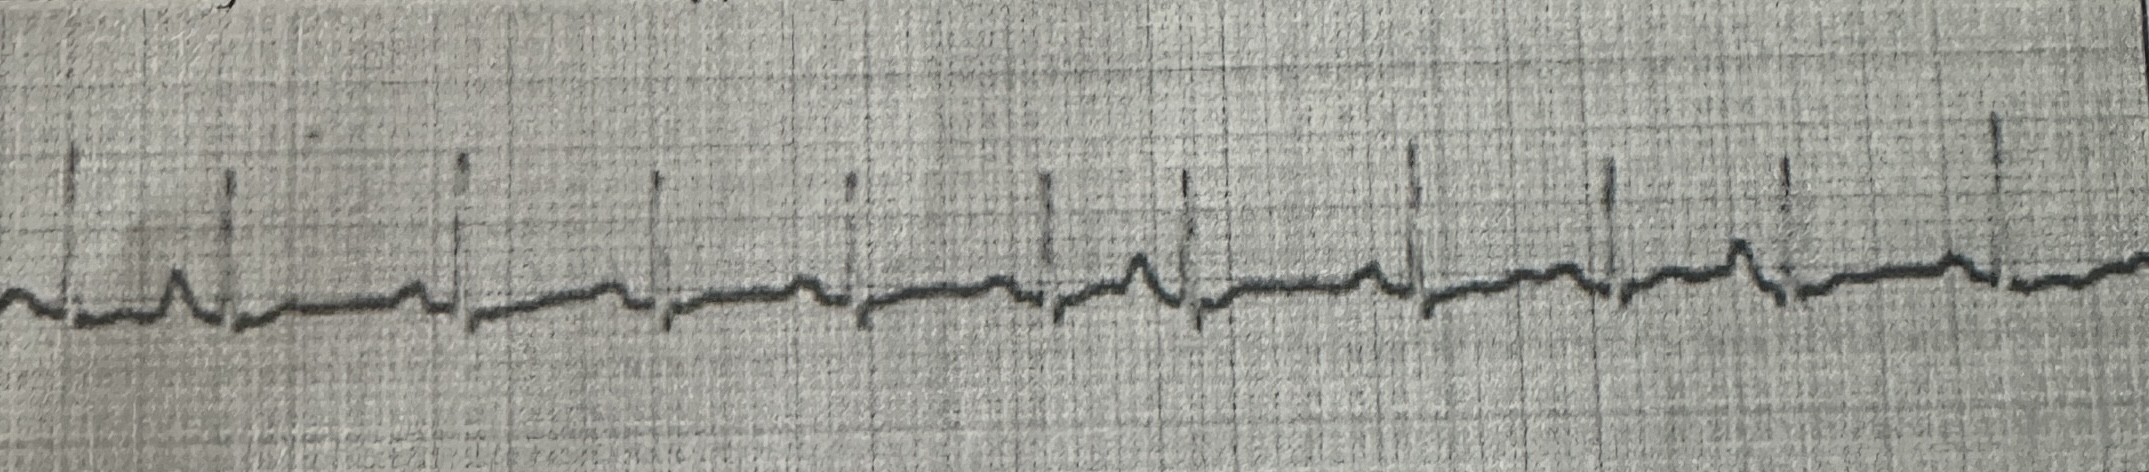

<p>identify this rhythm strip</p>

identify this rhythm strip

sinus tachycardia with premature atrial complexes (PACs)